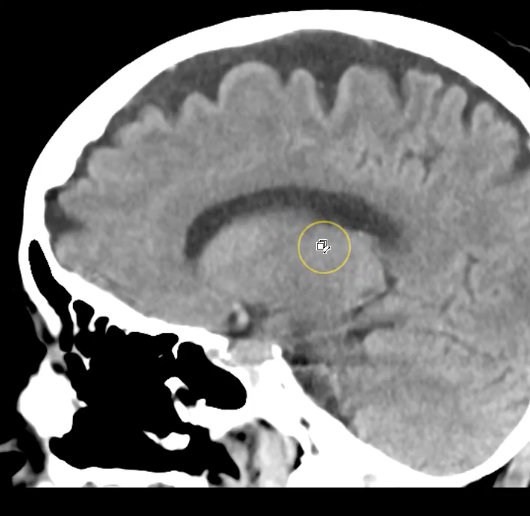

term image

calcified choroid plxus in lateral ventricles